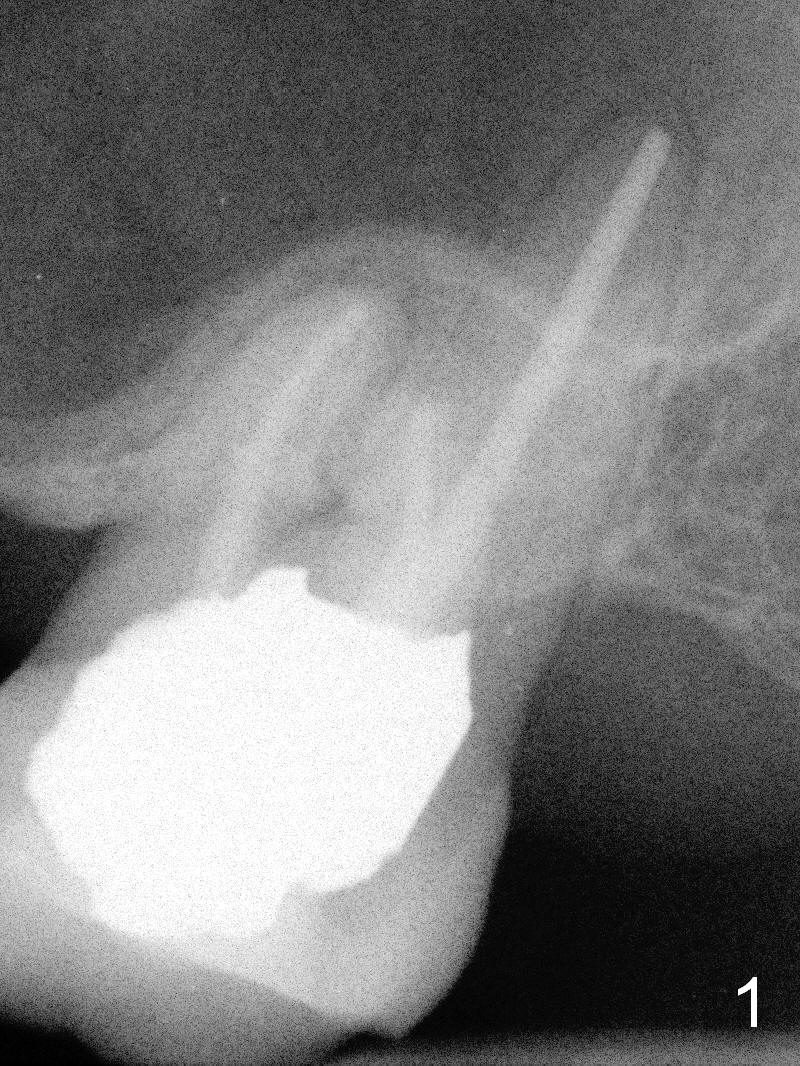

A 60-year-old man requests implant at #15, since the tooth with distal subgingival caries has kept fracturing in the last 4 years (Fig.1,2). Metronidazole will be used for socket disinfection. Since the socket is most likely large and single (fused roots), a large IBS implant (Fig.3,4: 6 or 6.5x9 or 11 mm) is to be placed following initial 7 mm depth of drilling or bone expansion (Fig.4). Prepare bone graft for sinus lift and gap closure. His bone is soft at #10; underprep is necessary at #15. An abutment is expected to be 6x4(3) mm (Fig.4). Since he is partially edentulous, an immediate provisional should be large enough to close the socket, but small enough not to be interfered with the partial denture on and off. Take photos of #10 to show no metal show.